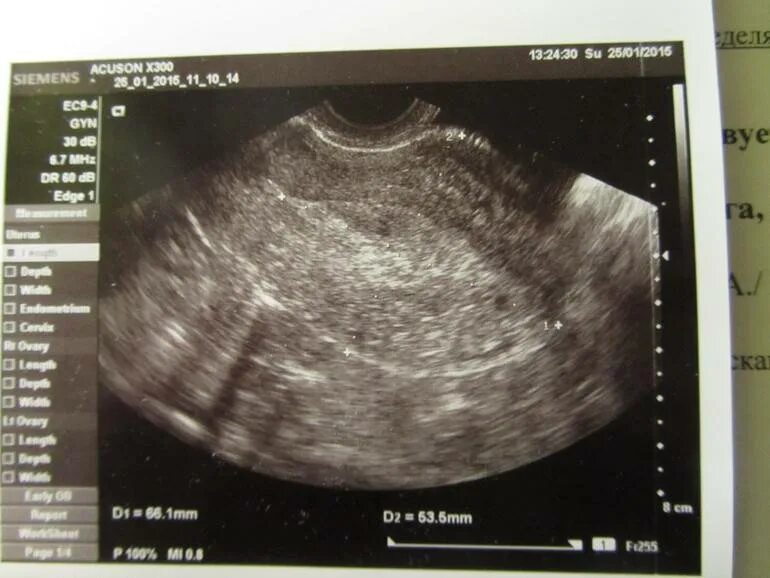

Когда можно идти на узи